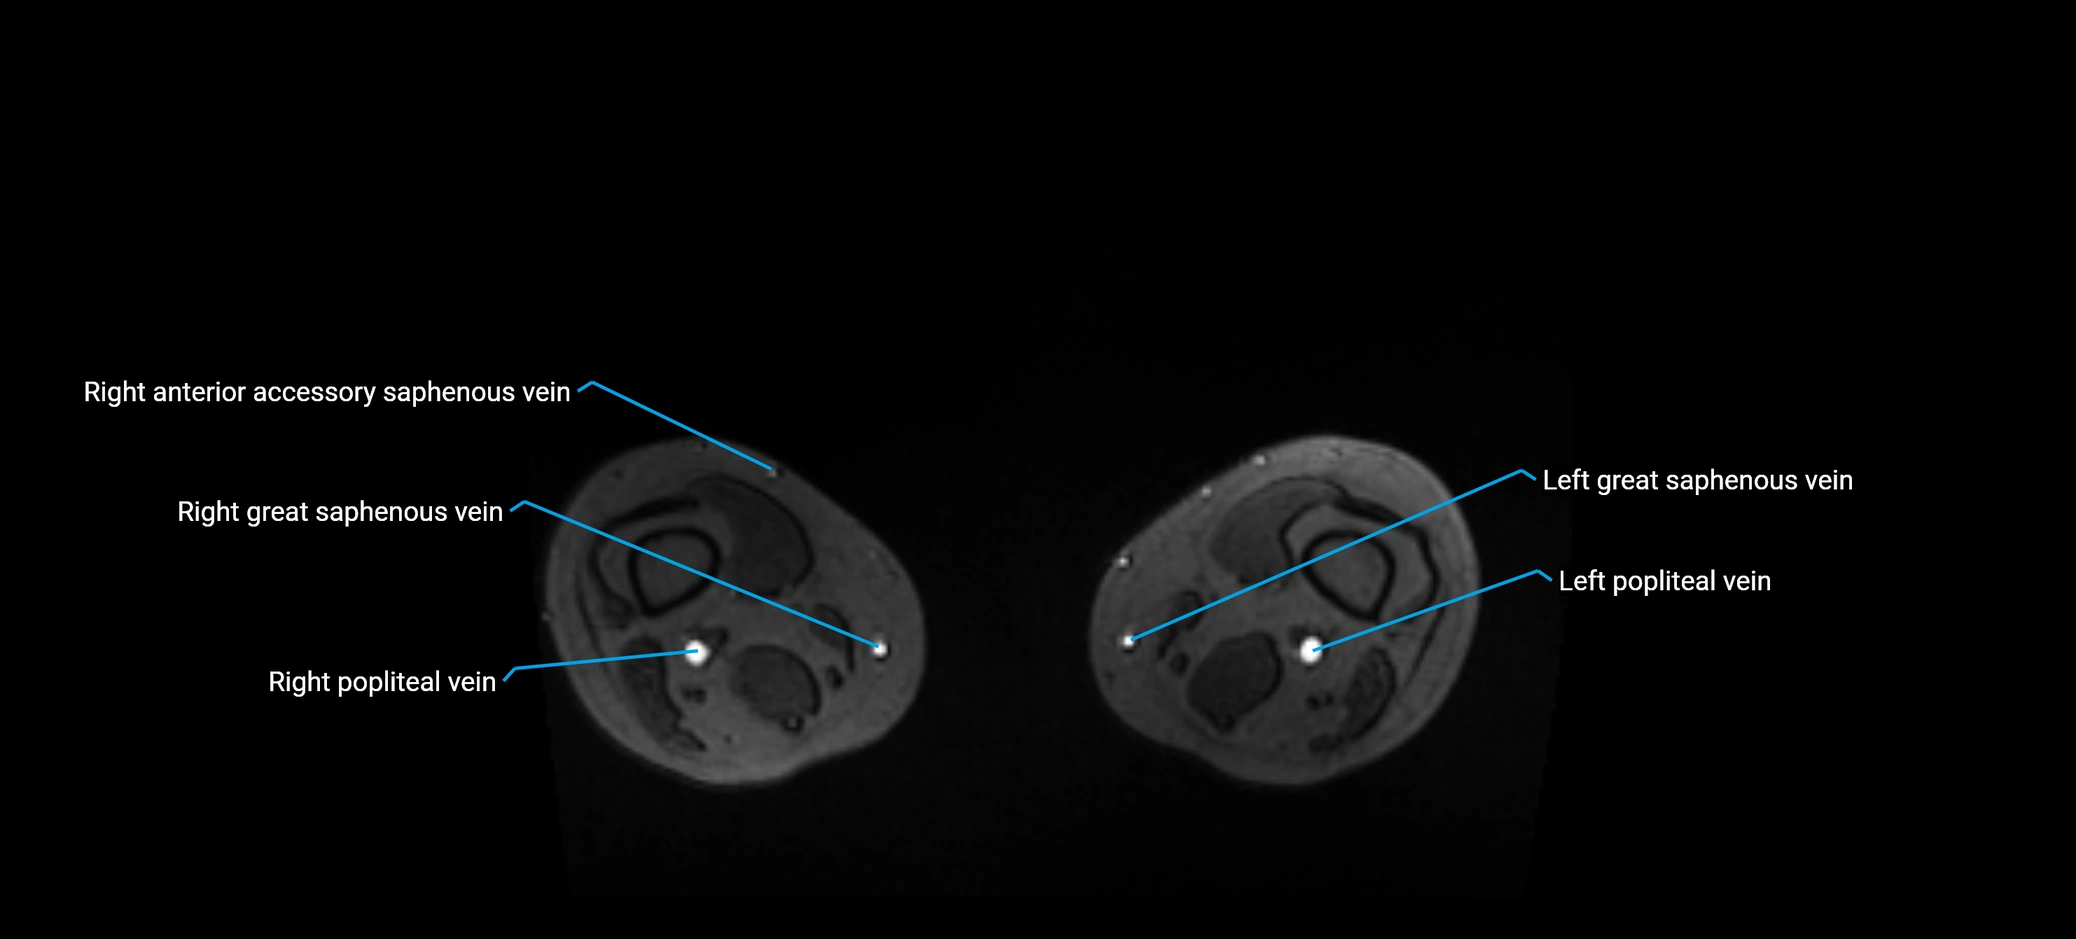

MRI image

image